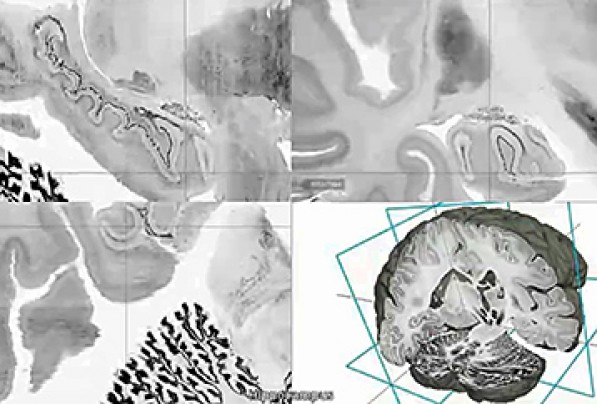

The digital three-dimensional model called "BigBrain" was produced from the thousands of sections made from the brain of a 65-year-old woman. Its resolution is finer than a human hair, so it can reveal clusters of brain. A 65-year-old woman’s brain was cut into 7,400 slices to create the most detailed three-dimensional atlas of the human brain ever made, bringing researchers one step closer to reverse-engineering the brain’s convoluted circuitry. Brain atlases are essential reference tools for researchers and physicians, to determine which areas are “l(fā)ighting up” during a task or thought process, or during image-guided surgery. The better the atlas resolution, the better doctors can target ever-smaller parts of the brain and their individual function. The atlas creators, who are from Canada and Germany, have made the ultrahigh-resolution model — 50 times more detailed than a typical scan — publicly available in a free online format. The authors also published their work in the journal Science on Thursday. The atlas, called BigBrain, offers a common basis for open, worldwide scientific discussion on the brain, said author Karl Zilles of the Heinrich Heine University Düsseldorf. Zilles pointed to a novel treatment for Parkinson’s disease called deep brain stimulation, where electrical impulses are sent through electrodes implanted into specific points in the brain. He said BigBrain may open the doors for more accurate localization of electrode placement and thus render treatment more effective. After staining and digitizing the thousands of plastic-wrap-like slices, the nearly cellular resolution map revealed the network of layers, fibers and microcircuits of the woman’s brain. While variation exists among brains, across ages and individuals, they have largely the same distribution of brain structures and anatomy, said author Alan Evans of McGill University’s Montreal Neurological Institute. There are “subtle shape changes among individuals,” but all atlases start from one representative brain and go from there. The team was chiefly limited by computing power and capacity. To map the human brain with 1 micron spatial resolution, which has been done for mouse brains, the atlas would take up 21,000 terabytes of data — essentially rendering it impossible to navigate. By comparison, BigBrain, with its 20 micron resolution, comprises about a terabyte of data. Prior MRI-based atlases had resolution of 1 millimeter. Richard Leigh, a Johns Hopkins neurologist, said he’s looking forward to test-driving BigBrain for his research on stroke recovery. With the microscopic detail available, Leigh can see which particular groups of neurons are growing through stroke treatment rather than just a general fuzzy area. Evans was in Seattle on Wednesday working with the Allen Institute for Brain Science. Created by Microsoft co-founder Paul Allen, who has committed $500 million since its start in 2003, the Allen Institute has assembled a less-detailed human brain atlas of its own. BigBrain is part of the European Union’s Human Brain Project that brings together specialists in neuroscience, medicine and computing to decipher the mysteries of the brain. President Obama announced in April an initiative to map the human brain, describing it as a way to discover cures for neurological disease and strengthen the economy. |